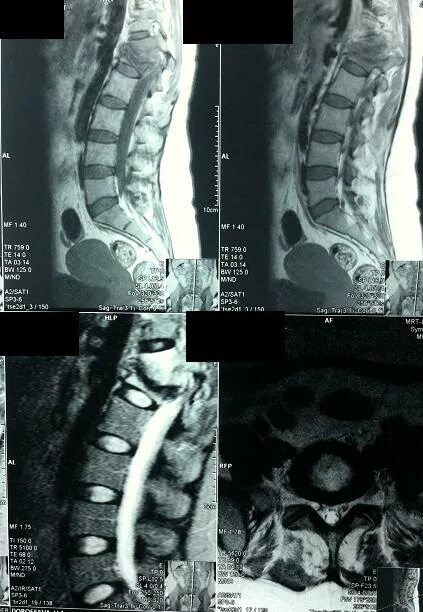

Перед мрт позвоночника можно кушать